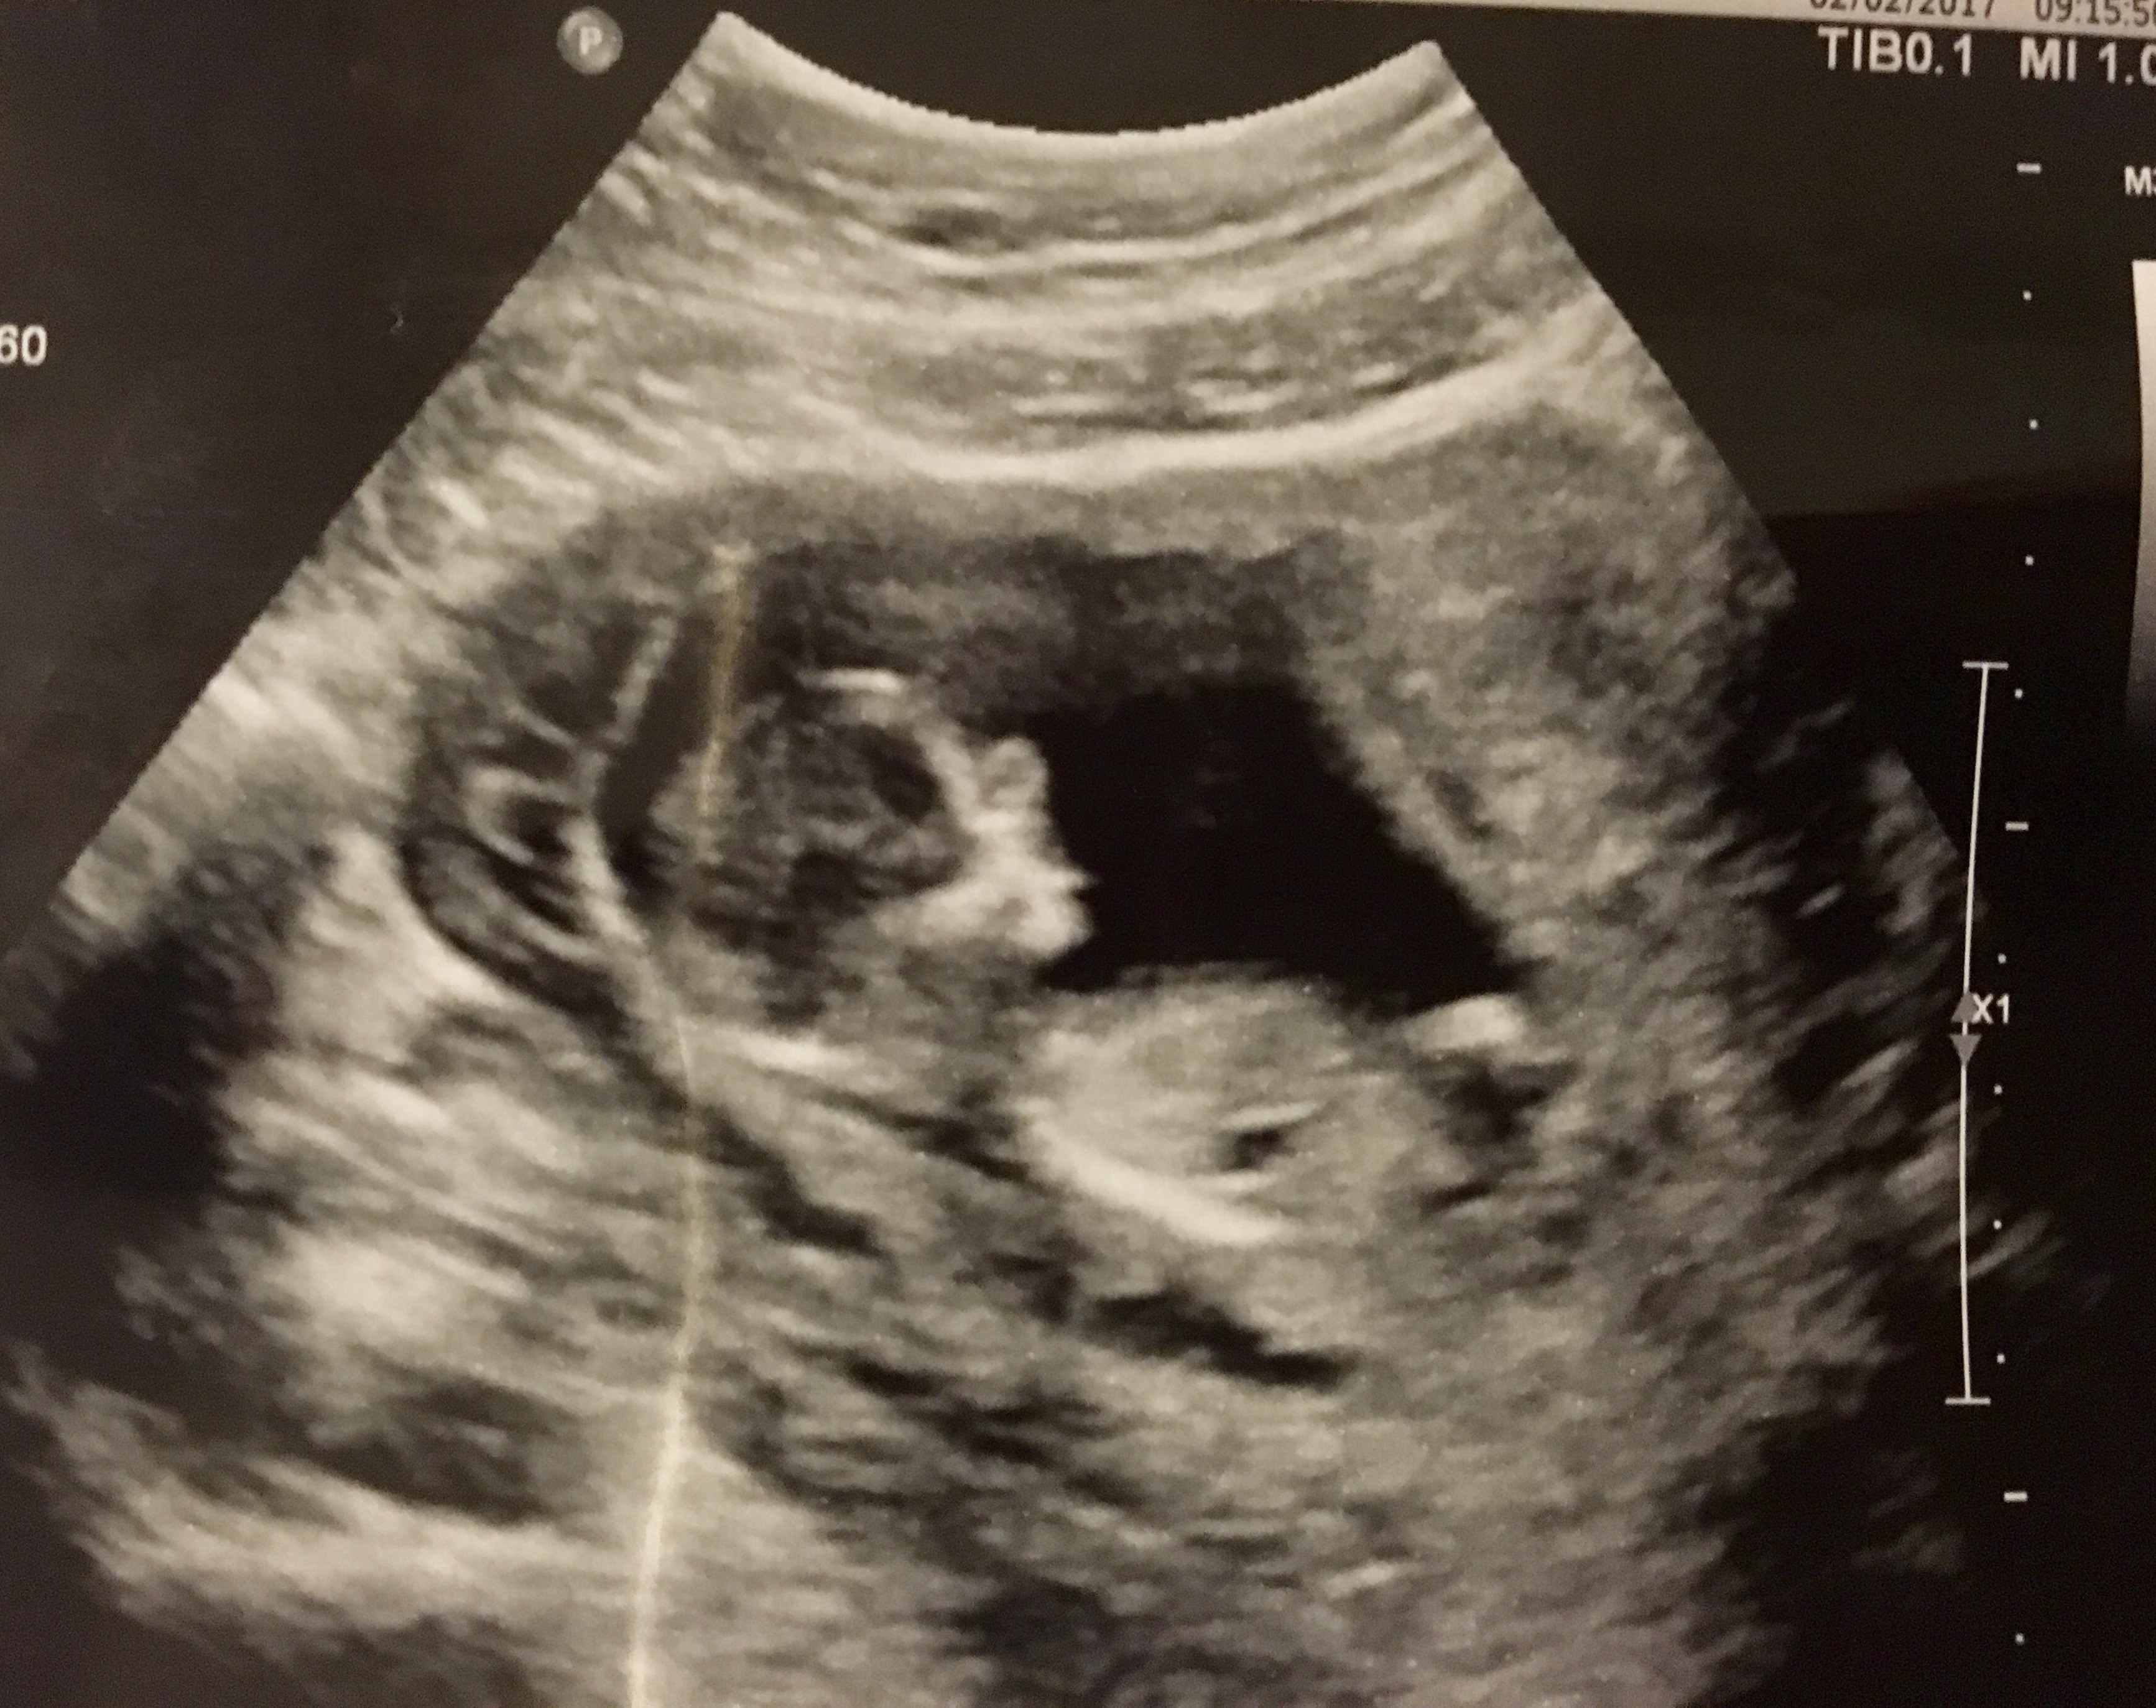

Hi- new to this forum. Just had my ultrasound today 12 wks 5 days. Any gender guesses???

Maybe boy, but I'm not really sure the nub is showing.

Boy

Bump!! Any more guesses?? Ultrasound tech said she thinks girl but I don't know!

Boy lean